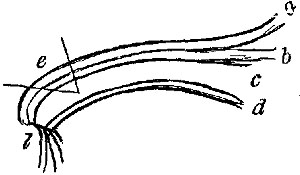

OPERATIONS ON THE EYE AND ITS APPENDAGES. | |

| Entropium and Ectropium—Trichiasis—Tarsal Tumours—On Lachrymal Organs—Mr. Bowman's Operation—Pterygium—Strabismus, convergent and divergent—Paracentesis of the Anterior Chamber—Operations for Cataract by Displacement, Solution, and Extraction—Various methods of Extraction—Operations for Artificial Pupil—Iridesis—Corelysis—Iridectomy—Excision of Staphyloma—Excision of Eyeball, | 151-174 |